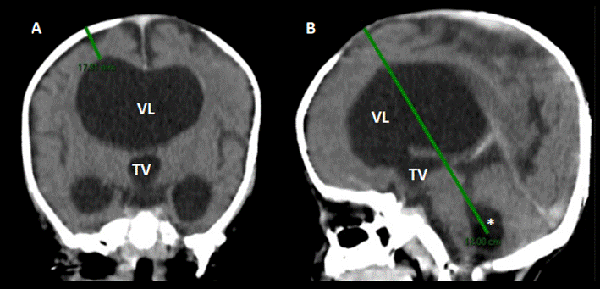

Todos los procedimientos se realizaron bajo anestesia general. Previo ingreso a quirófano (entre 3 y 6 hs), se cierra el DVE y se realiza una tomografía computada para llevar a cabo la planificación quirúrgica con base en la anatomía del paciente. Las mediciones que se toman desde la tabla externa de la calota son: a) el espesor del parénquima que nos indica la profundidad para llegar al ventrículo lateral y b) la longitud total que existe hasta la mitad del cuarto ventrículo, sitio en el cual quedará alojado el catéter (Figura 3).

Figura 3: TC pre quirúrgica utilizada para planificación quirúrgica A) corte coronal en el cual se observa el espesor del parénquima cerebral (línea verde) y la distancia que existe entre la tabla externa de la calota y el ventrículo lateral derecho, B) corte sagital en el cual se mide la longitud del catéter al cuarto ventrículo (línea verde). VL: ventrículos laterales TV: tercer ventrículo (*): cuarto ventrículo.